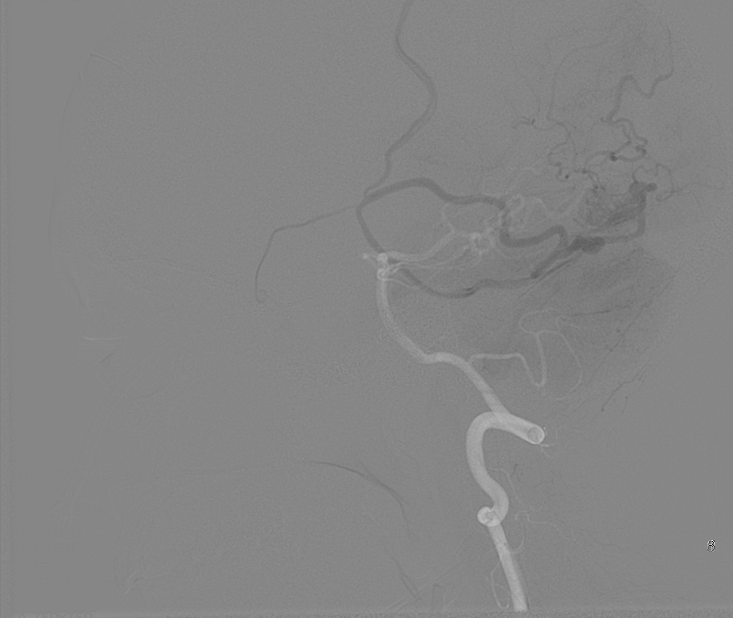

We chose FastICA to define the unmixing function and applied it on 19 DSA image series of subjects with an AVM. The series were composed of 12 to 38 images showing the malformations at different time points and were acquired at a low frame rate of 1.5fps to 6fps. As shown in Figure 2, the function was capable of decomposing the phases of vascular flow. We also generated phase-constrained color-coded overlays for DSA image series through the combination of the recovered sources and vessel masks, leading to a visualization where contrast flow appears progressively and is classified as artery, nidus and capillary, or vein. An example of this visualization is shown in Figure 3.